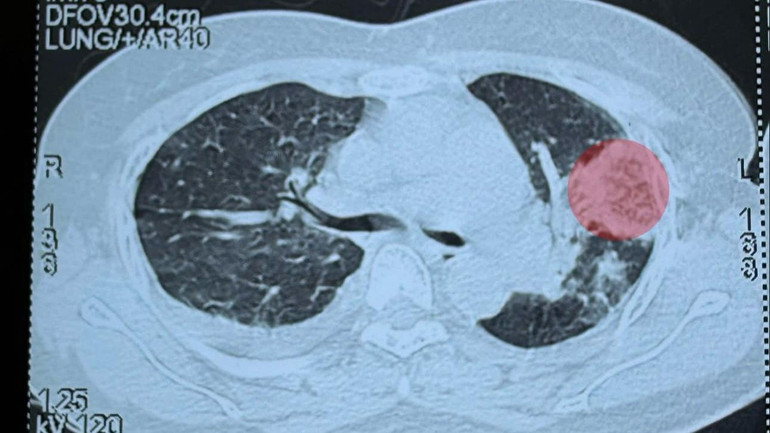

Ngày 29/5 bệnh nhân chuyển đến Bệnh viện Bệnh Nhiệt đới Trung ương khám và điều trị. Khi nhập viện, bệnh nhân được chẩn đoán là sốt xuất huyết ngày thứ 7, có tình trạng bội nhiễm. Chụp cắt lớp phổi cho thấy các đám đông đặc rải rác, có nhiều ổ áp-xe ở trong phổi...

| Ổ áp xe trong phổi bệnh nhân trên phim chụp. |